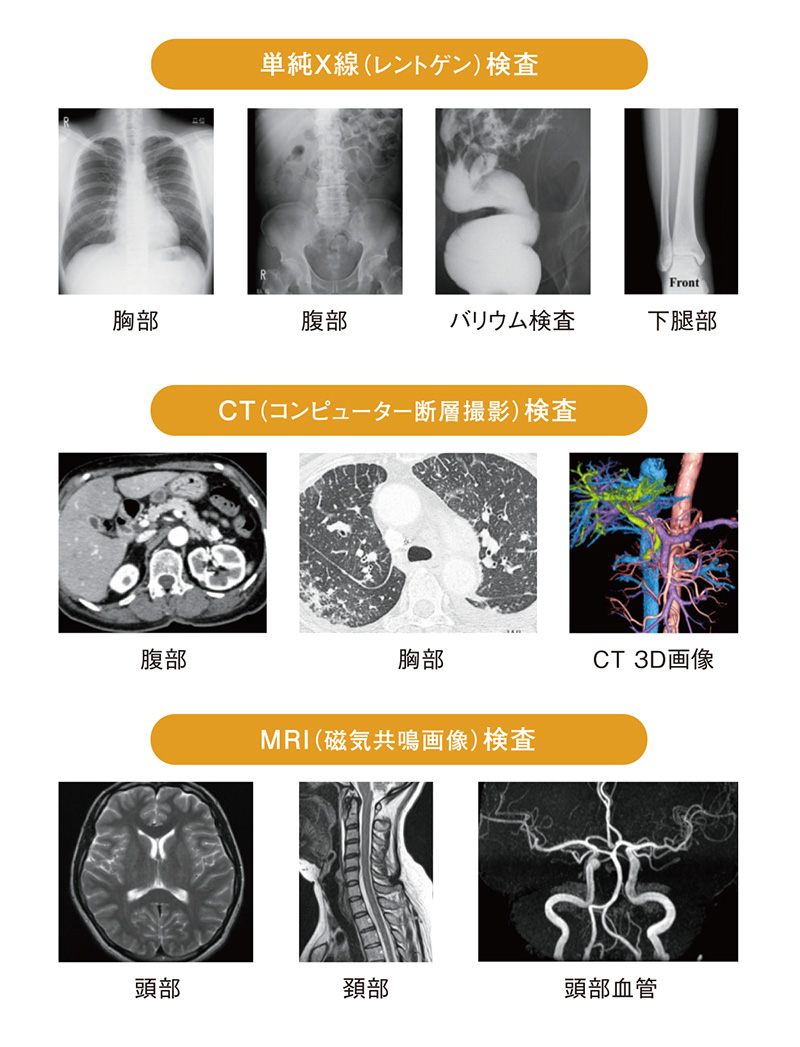

放射線診断学は単純X線やCT、核医学などの放射線を用いた検査以外に、超音波や磁気共鳴検査(MRI)などの放射線を用いない画像検査も含まれ、最近では画像診断学とも言われています。技術の発展に伴い画像診断学の進歩は目覚ましく、ほぼすべてのがん診療において画像診断の果たす役割は極めて大きなものとなっています。これらの画像検査を司り、頭から足先まで全身を診る放射線診断医(画像診断医)は、体の輪切りの画像や造影剤投与前後での変化を調べることで、病気の種類を推察したり、腫瘍の形態や位置・広がり、正常組織との関係を調べるなどといった的確な画像診断はもとより、被爆や侵襲性など各検査法の特徴を考慮して、適切な検査法、撮像方法や部位を決定・推奨することなどを行っています。

皆さん、CT検査の画像を見たことはありますか?CT画像はよく「体の輪切り画像」と表現されます。近年のCT装置の進歩は著しく、専門的な画像処理を施すことで「輪切り画像」だけでなく、様々な画像表示を行うことができるようになりました。上に示すのはほんの一例ですが、「3D画像」といって患者さまに疾患を説明する際や手術の前に綿密なシミュレーションを行う際に役立つものです。白黒のCT画像を用いて作成するのですが、色付けをすることで誰にでも疾患を理解しやすい画像となっていますこのように、現代の医療において患者様の病気を早期発見し、安心して安全に治療を受けていただく上でCT検査は必要不可欠となっています。

皆さん、CT検査の画像を見たことはありますか?CT画像はよく「体の輪切り画像」と表現されます。近年のCT装置の進歩は著しく、専門的な画像処理を施すことで「輪切り画像」だけでなく、様々な画像表示を行うことができるようになりました。上に示すのはほんの一例ですが、「3D画像」といって患者さまに疾患を説明する際や手術の前に綿密なシミュレーションを行う際に役立つものです。白黒のCT画像を用いて作成するのですが、色付けをすることで誰にでも疾患を理解しやすい画像となっていますこのように、現代の医療において患者様の病気を早期発見し、安心して安全に治療を受けていただく上でCT検査は必要不可欠となっています。